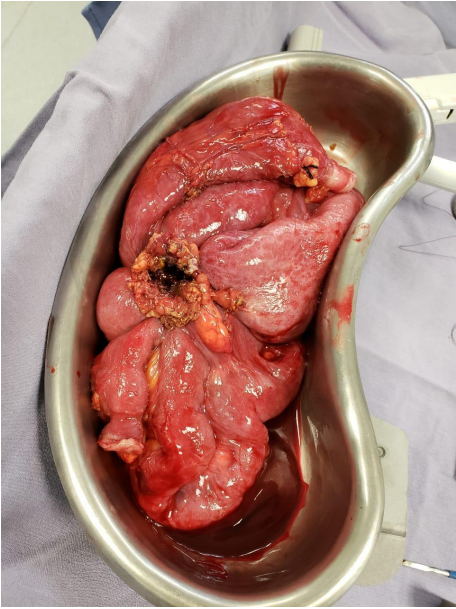

Por los hallazgos, se decidió realizar una laparotomía exploradora. Encontrando una fístula entero-cutánea y entero-entérica formada por un conglomerado de asas intestinales. Se encontraron 5 asas comunicadas entre ellas (Foto 3); el extremo proximal a 80cm del ángulo de Treitz y el extremo distal a 140 cm de la íleo-transverso anastomosis; se reconoce recaída tumoral en la fístula (anatomía patológica extemporánea: Adenocarcinoma). Se resecó el trayecto fistuloso en la pared abdominal y las asas intestinales involucradas (Foto 4).

Foto 4: Pieza quirúrgica resultado de resección de conglomerado de asas intestinales y fistula entero-cutánea/entero-entérica